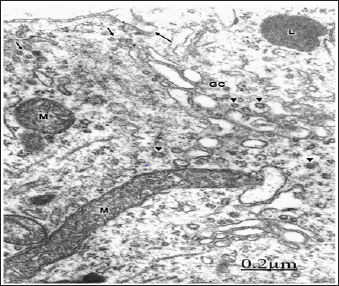

Figure 4: Congenital hydrocephalus. Right parietal cortex. The plasma membrane exhibits a deep invagination (long arrow) and formation of endocytic vesicles (short arrows) directed toward the swollen Golgi complex (GC). A lyso-some (L), moderately swollen and dark mitochondria (M), numerous Golgi vesicles and clathrin-coated vesicles (ar-rowheads) also are seen. X 60.000.

The plasma membrane shows deep invaginations and formation of numerous endocytic vesicles directed toward the endoplasmic reticulum and the Golgi apparatus [68]. The lysosomes show fragmented limiting membrane (Figure 4). In congenital hydrocephalus in neonate patients we are dealing with immature plasma membranes, characterized by changes in the integral membrane proteins, cholesterol domains, and in certain carbohydrates residues and anionic sites [69]. These different molecular compositions of immature plasma membranes explain its high sensitivity to injury factors. In hypertensive congenital hydrocephalus, the pressure exerted by the non-circulating cerebrospinal fluid induces plasma membrane fragmentation, and enlargement of intracellular nerve cell compartments. In addition, the presence of oedematous mitochondria evinces a disturbed energy metabolism.